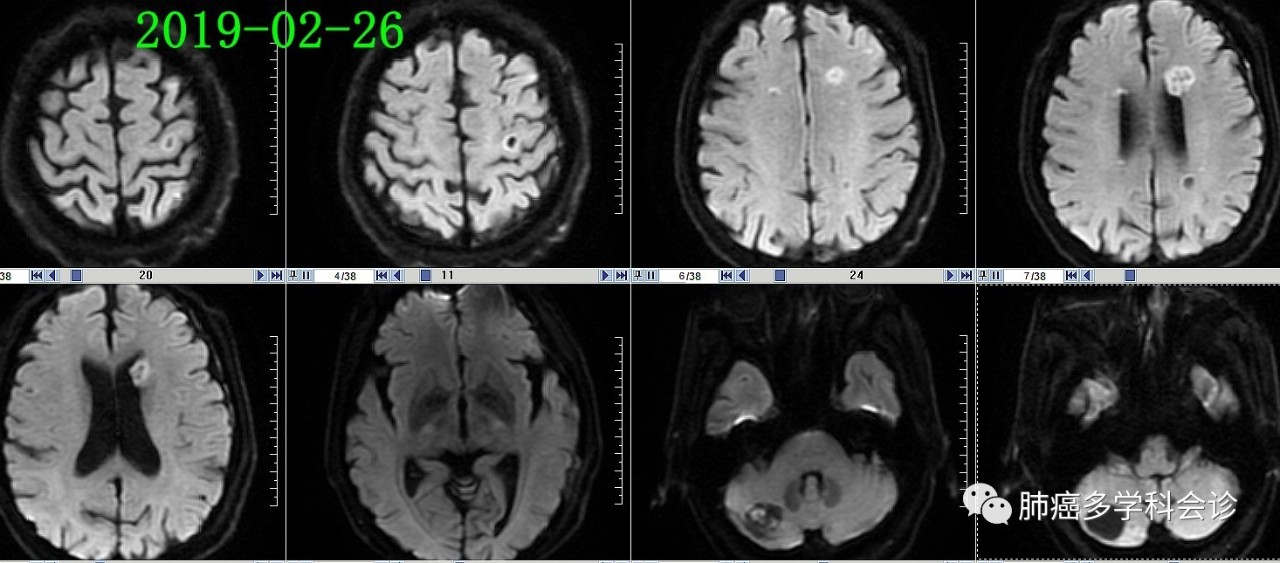

4.jpgMRI 扫描发现多发脑转移:5.jpg